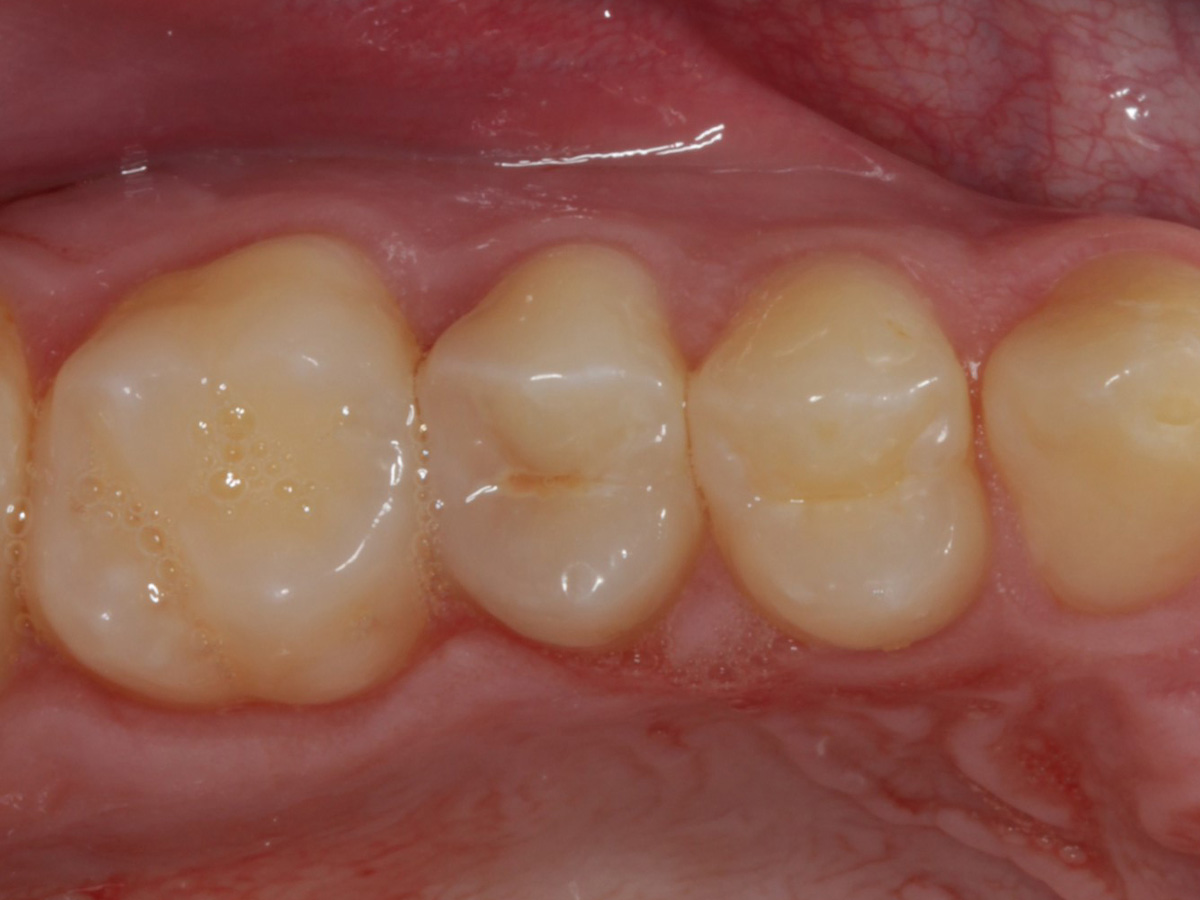

Abbildung 2

Intakte Kaufläche